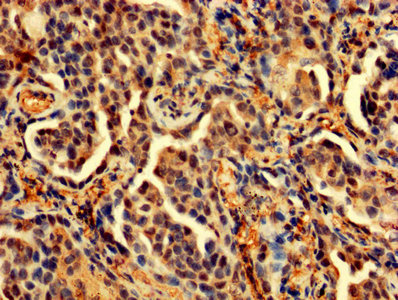

IHC image of CSB-PA04874A0Rb diluted at 1:200 and staining in paraffin-embedded human liver cancer performed on a Leica BondTM system. After dewaxing and hydration, antigen retrieval was mediated by high pressure in a citrate buffer (pH 6.0). Section was blocked with 10% normal goat serum 30min at RT. Then primary antibody (1% BSA) was incubated at 4°C overnight. The primary is detected by a biotinylated secondary antibody and visualized using an HRP conjugated SP system.